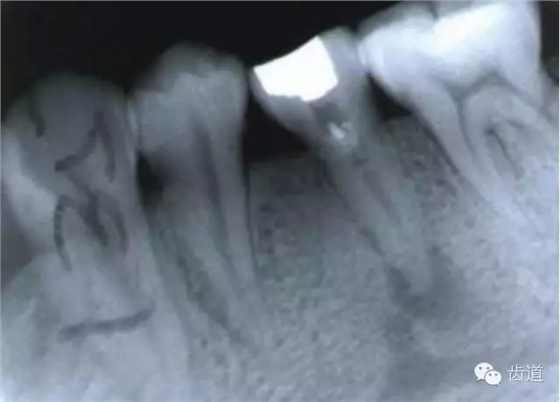

左上4鑄造樁側(cè)穿

左上5牙頸部側(cè)穿

左下6底穿

左上6底穿